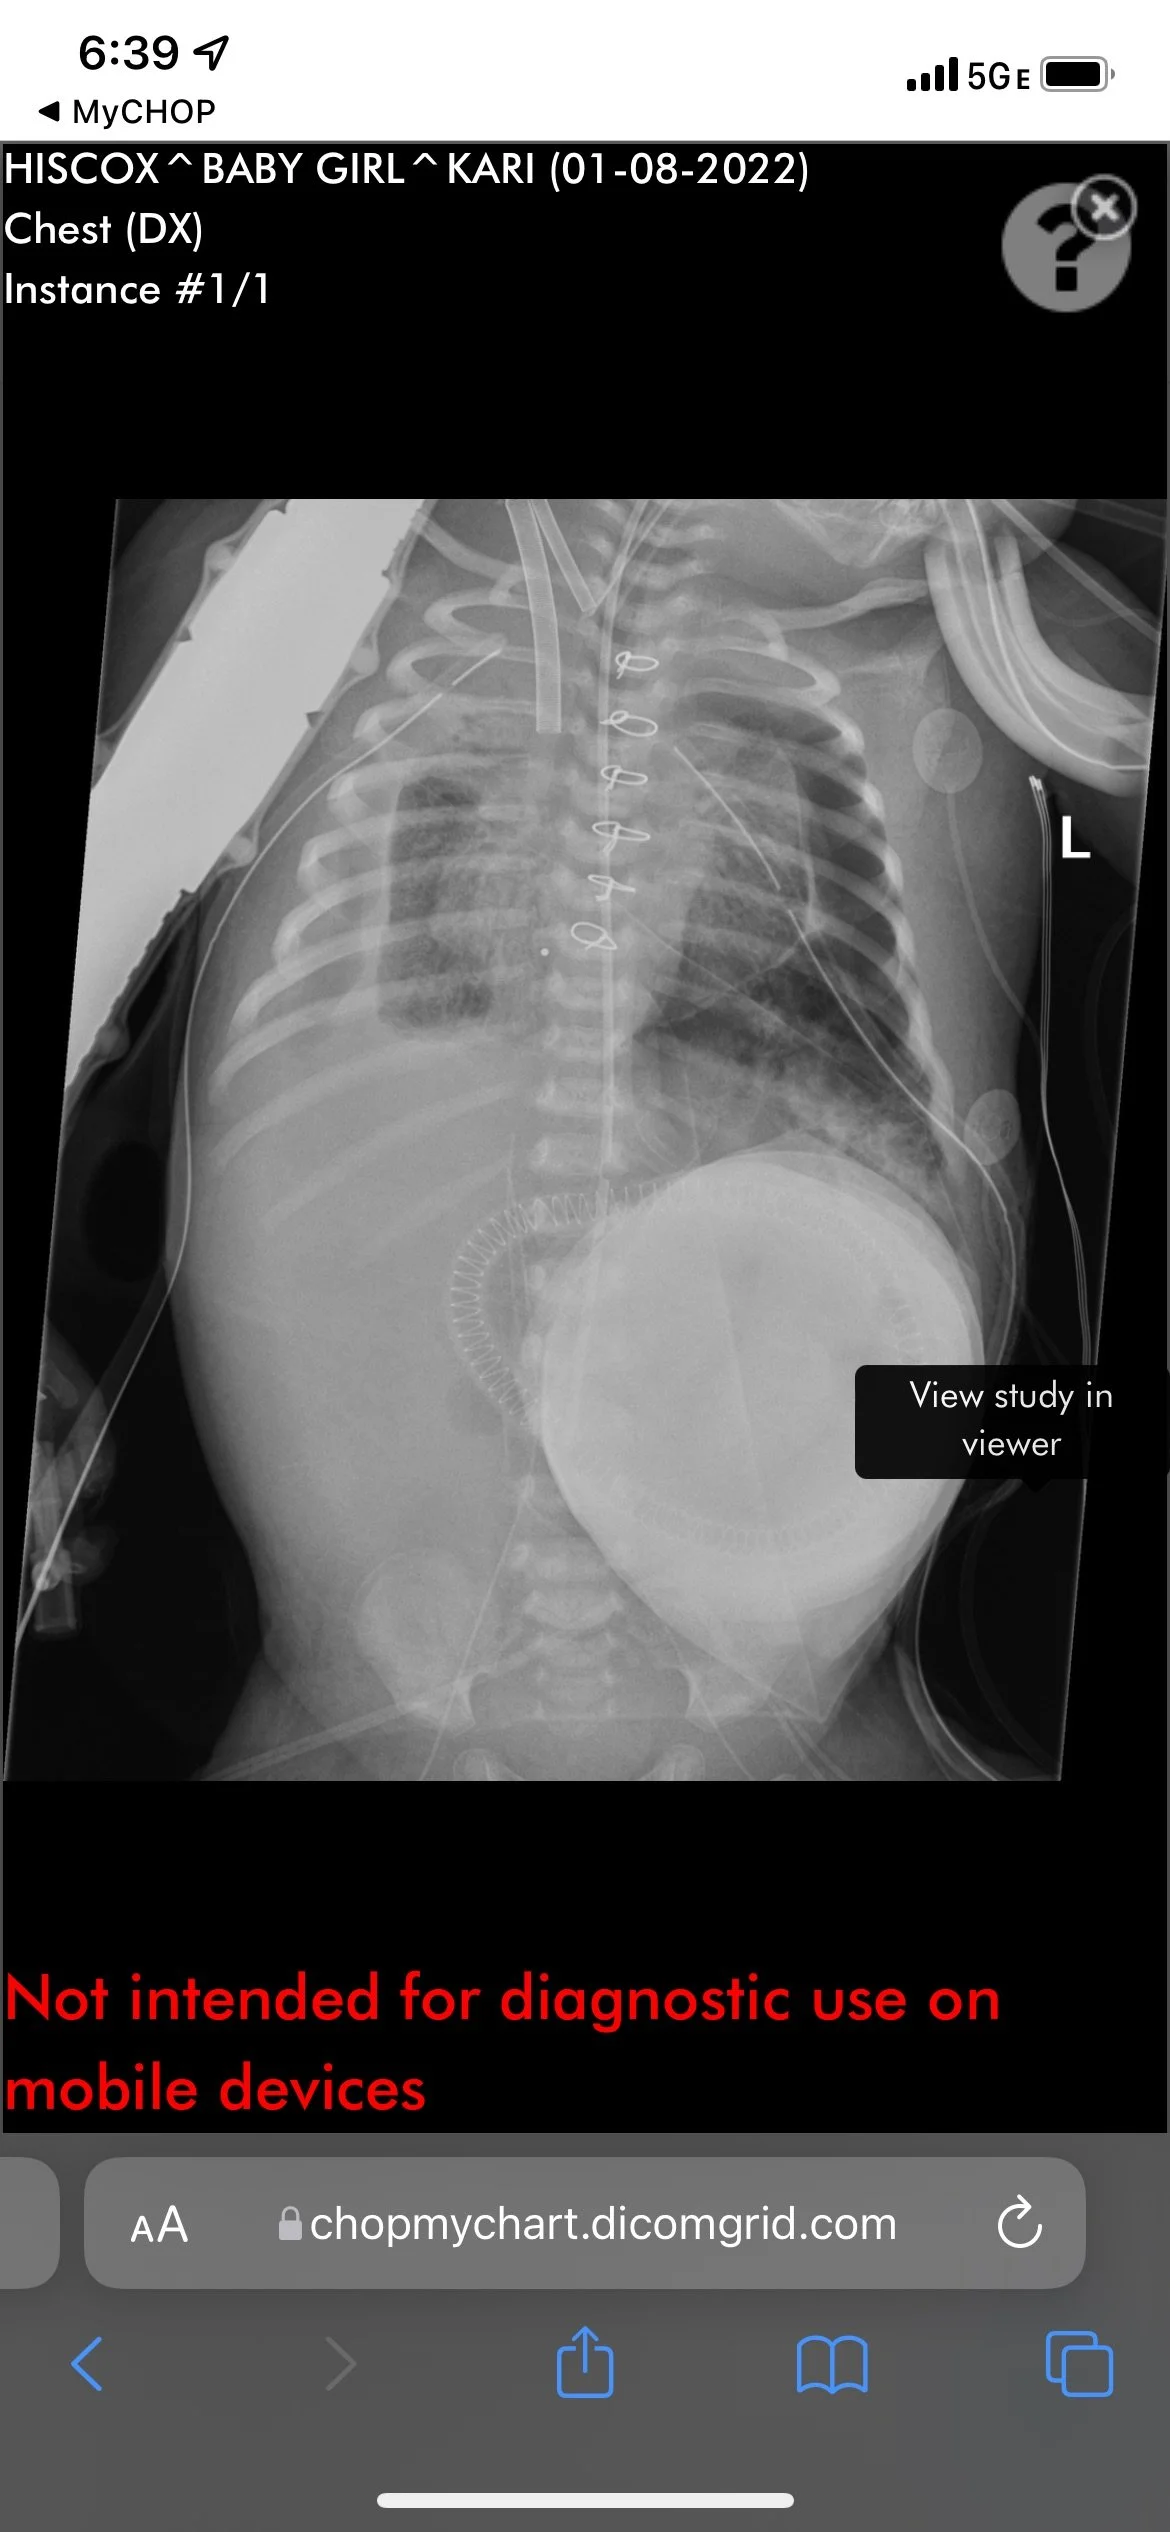

Her Progress on ECMO

Over the coming weeks, we spent hours by Brighton’s side in the NICU reading to her, getting to know her bedside staff, trying to take occasional small excursions out into Philadelphia (mostly for sandwiches at Middle Child), but were also starting to get anxious about her progress. Babies with CDH typically have their repair surgery within the first week or two of life, and it’s not good to stay on ECMO for more than a couple of weeks. We became hyper-focused on her chest x-rays which were “whited out” and not showing any open lung. Brighton was stable as long as she was on ECMO, but very sick. And ECMO is not something people can last on forever.

Because ECMO involves pumping and oxygenating your blood completely through a machine, they have to use blood thinners to keep the machine working properly. But blood doesn’t like to be outside the body and they were carefully looking for clots in the circuit. And those clots can break loose and cause problems. For Brighton, micro emboli, small blood clots, were getting stuck in her outer extremities, causing stress on her fingers and toes which began to look discolored from poor blood flow. The doctors were focused on her lungs and really could not do much about her fingers and toes while she remained on ECMO. The priority was getting her off ECMO. After expanding her set of machines to include dialysis to manage some fluid imbalances (she was now under the supervision of 3 full-time nurses), they began to see progress with her lungs on her x-rays. It was time to try and get her off of ECMO and move onto her CDH repair surgery.